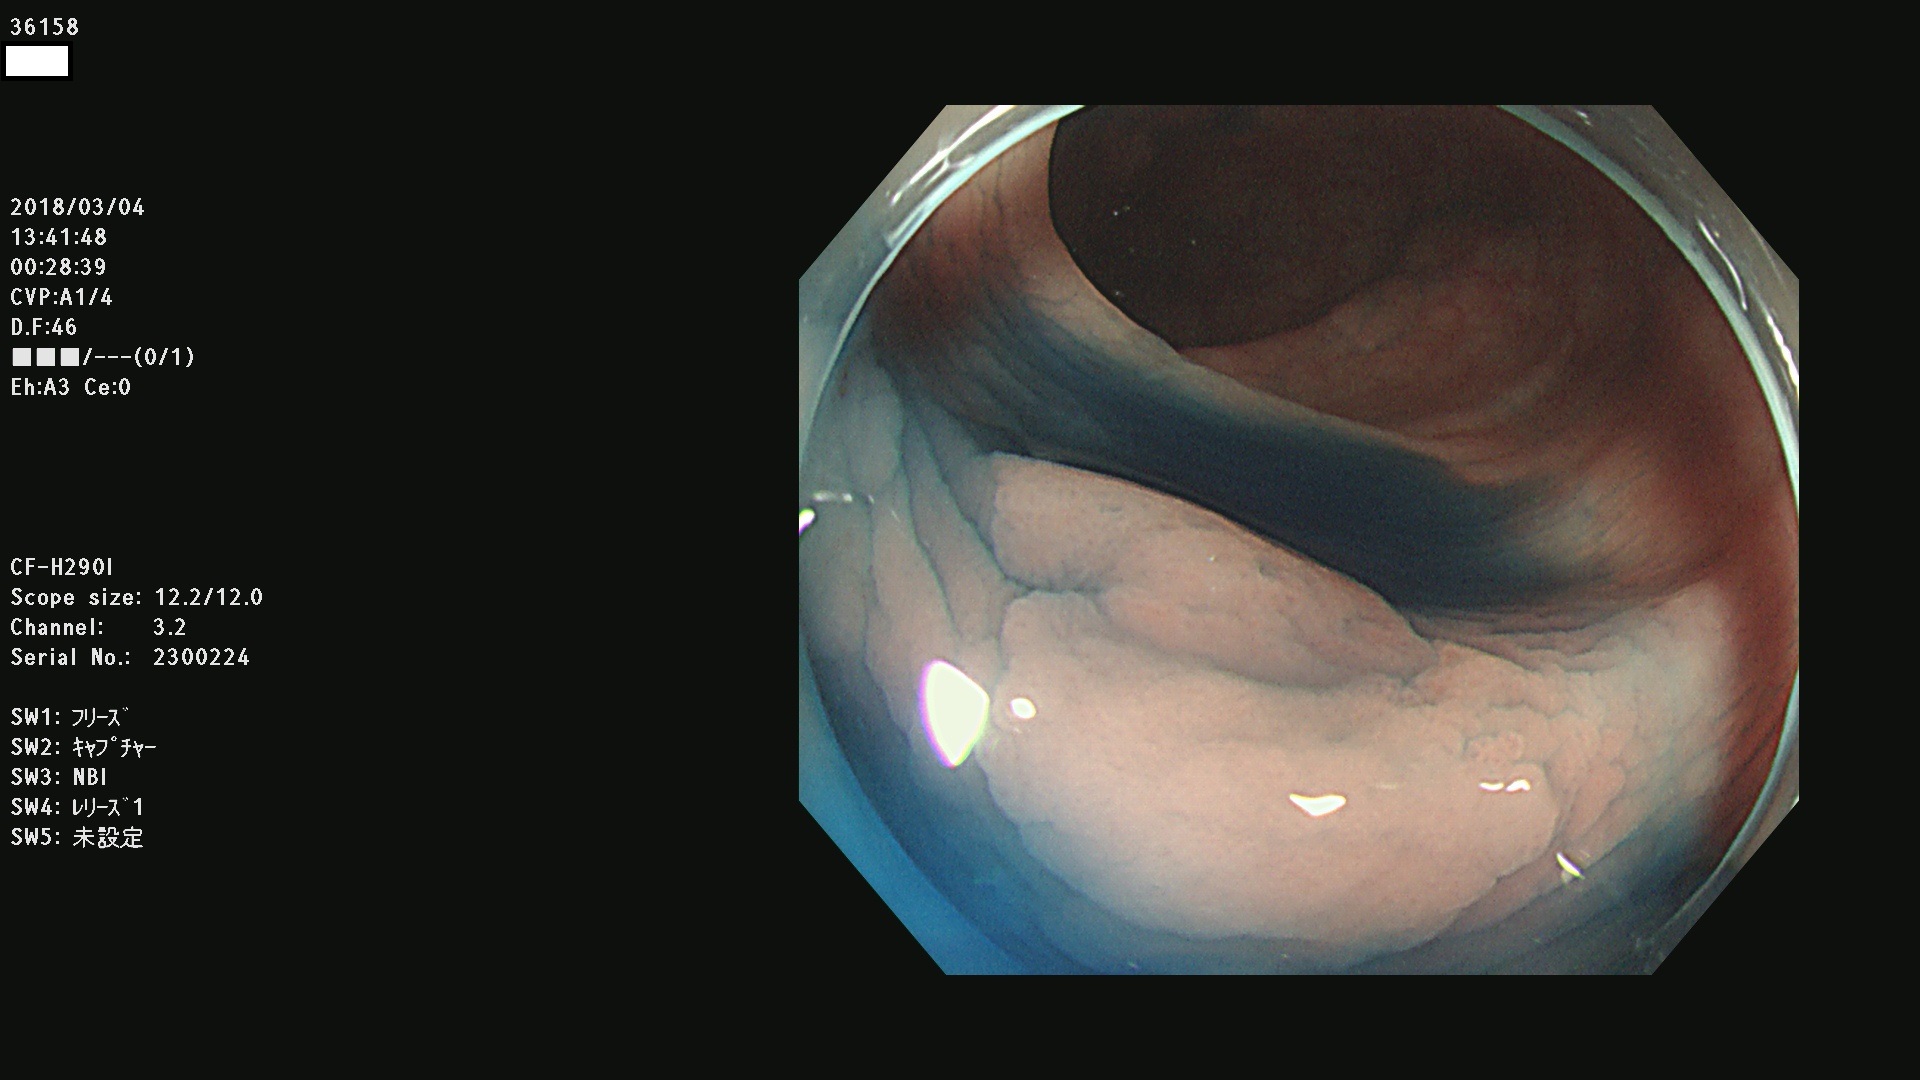

発見困難で危険性の高い平坦型病変(上記100名より抽出) ![]()